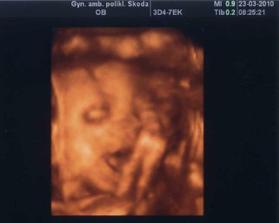

23.03.2010 25t + 2 máme cca 620g, vyšetření na cukrovku dopadlo dobře, dostali jsme pochvalu, máme prý výukové srdíčko tak byla mamka mooooc šťastná 🙂